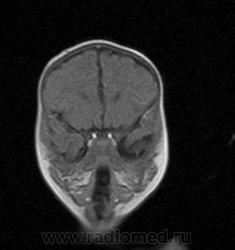

МРТ головного мозга

Ребенку 4 месяца, была внутриутробная инфекция и как следствие перенесенная гипоксия гол. мозга. На данный момент неврологи поставили диагноз задержка психомоторного развития.

УЗИ показало только пограничные размеры боковых желудочков.

МРТ - признаки дисплазии мозолистого тела. Врача результат МРТ почему то не смутил, по его словам мозг злоров. Причину задержки развития не установили. Лечащий врач сам удивляется и не может нам назвать причину (прошли уже два курса лечения).